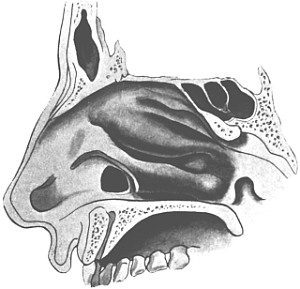

| 345. | Catheterizing the Sphenoidal Sinus | 654 |